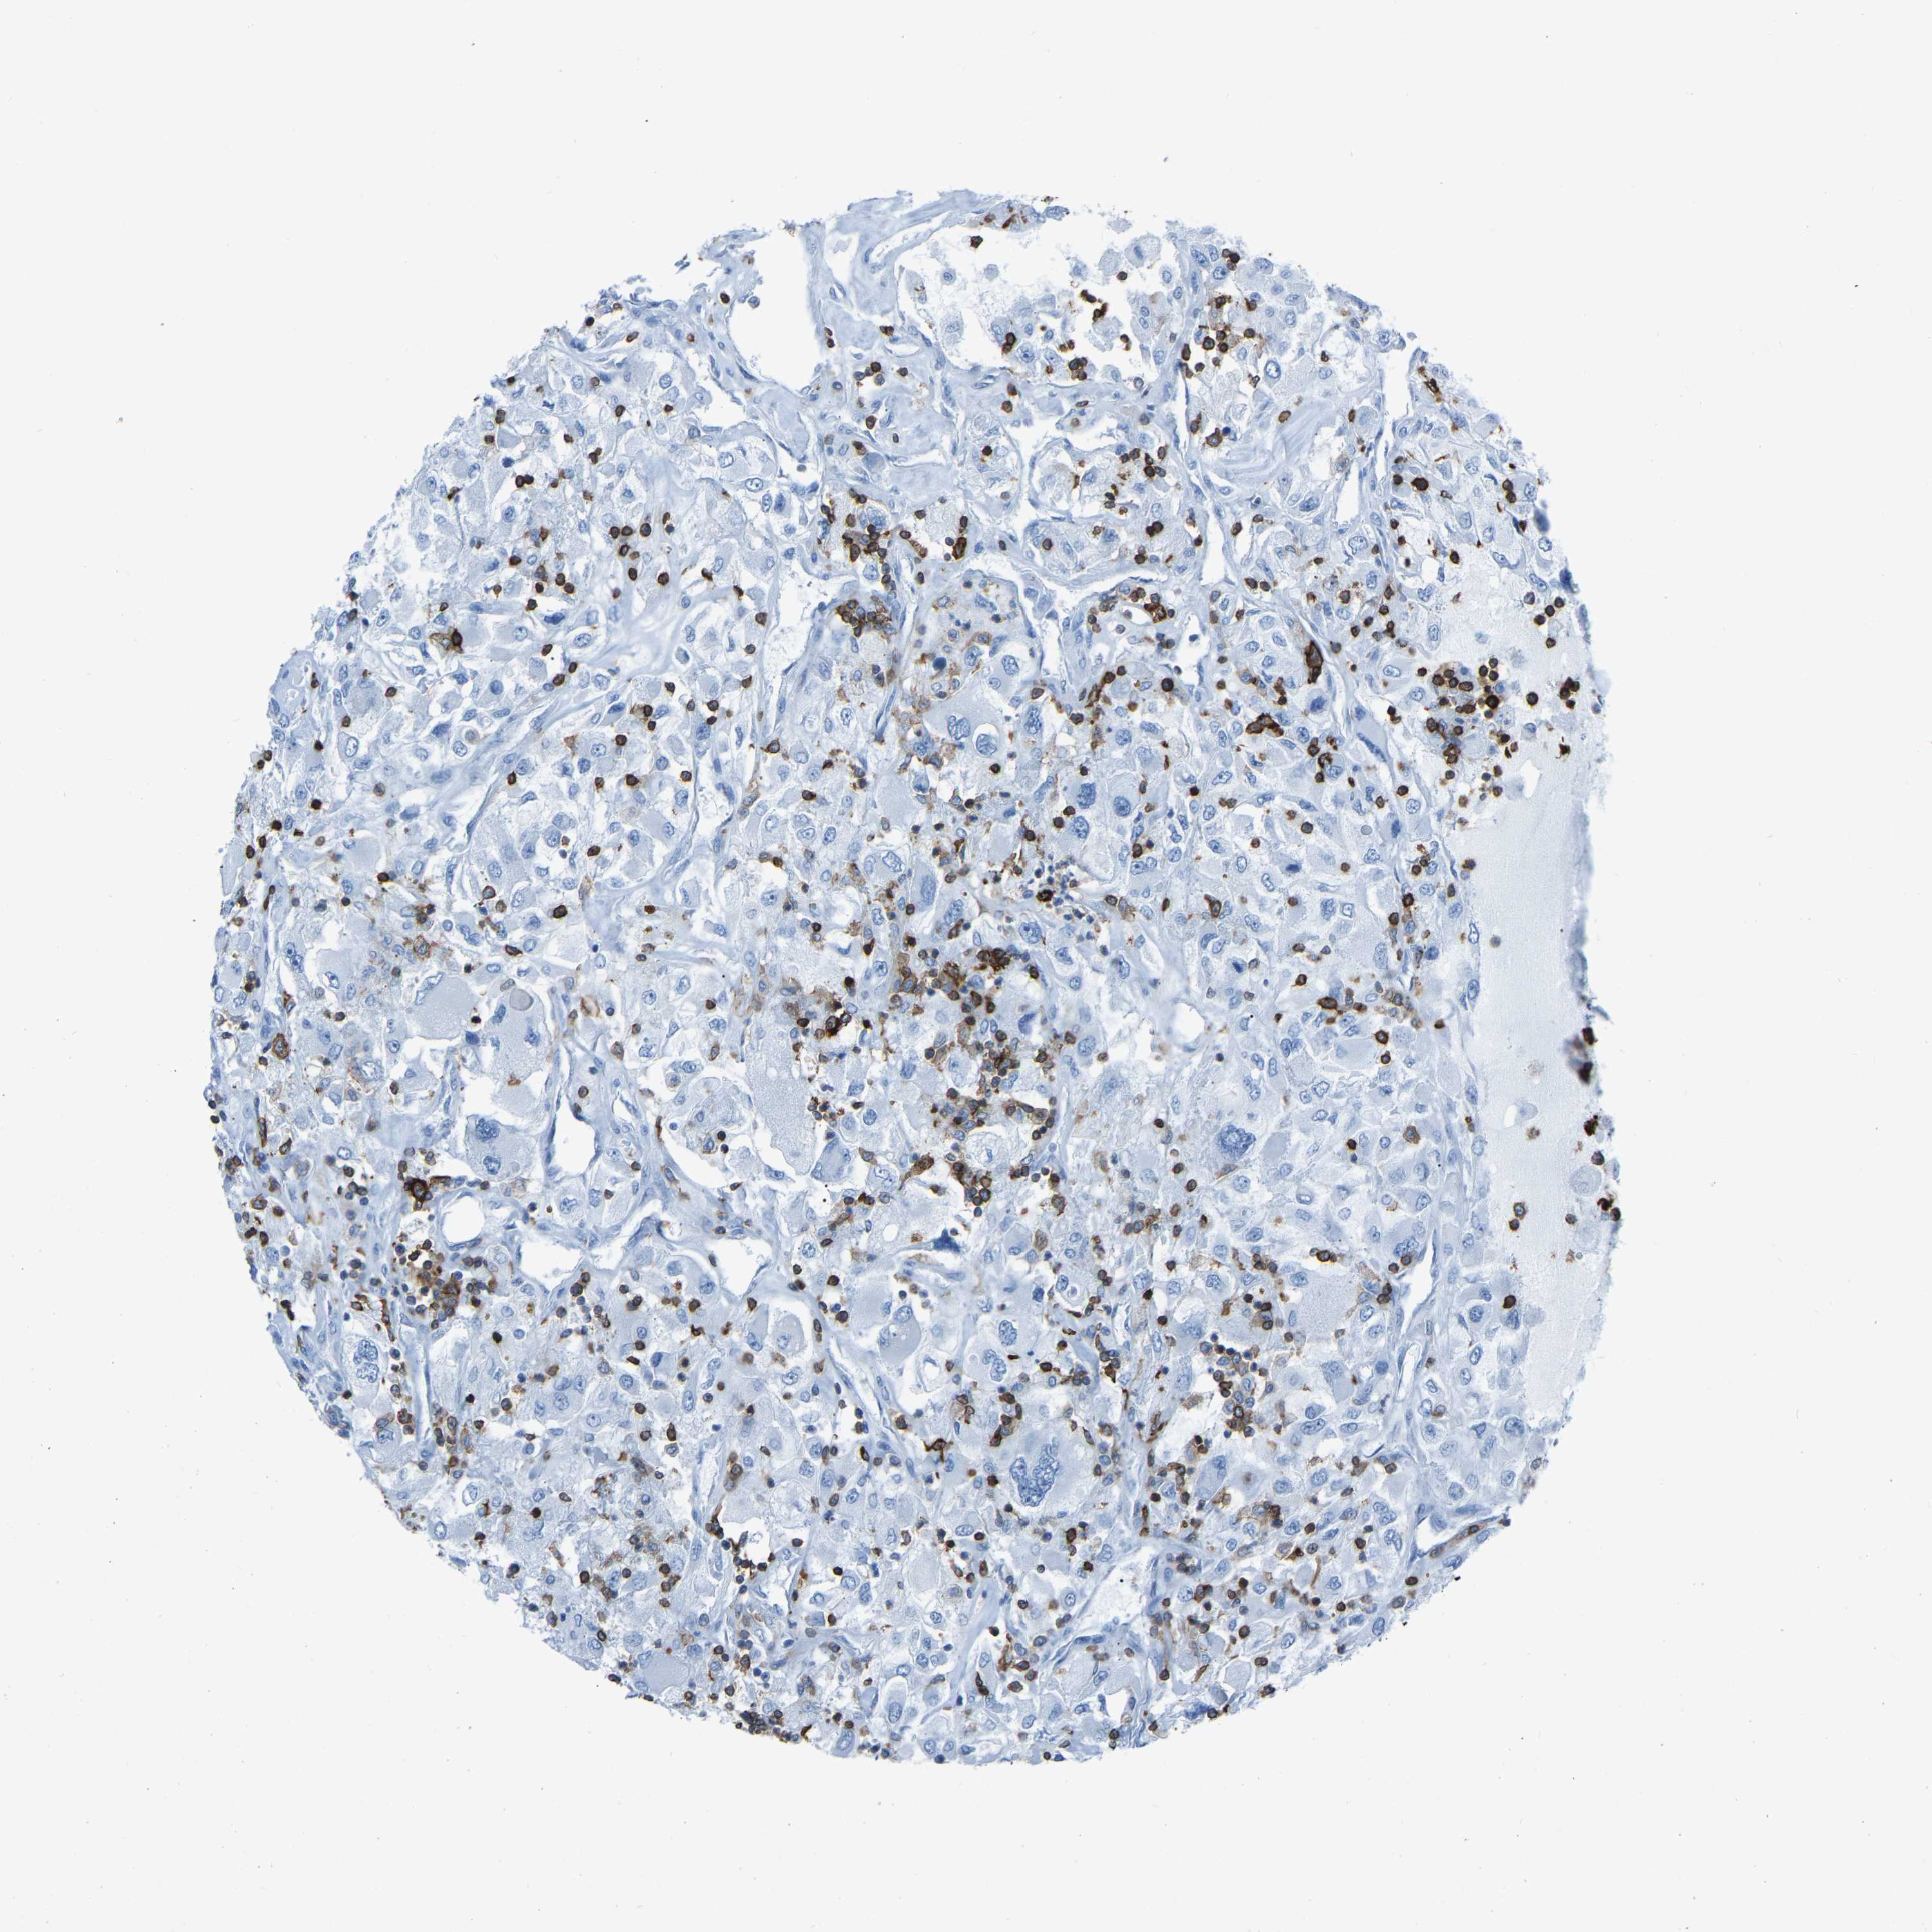

CANCER RENAL CANCER Show tissue menu

KICH TCGA KIRC TCGA KIRC VALIDATION KIRP TCGA PROTEIN RCC CPTAC PROTEIN EXPRESSION